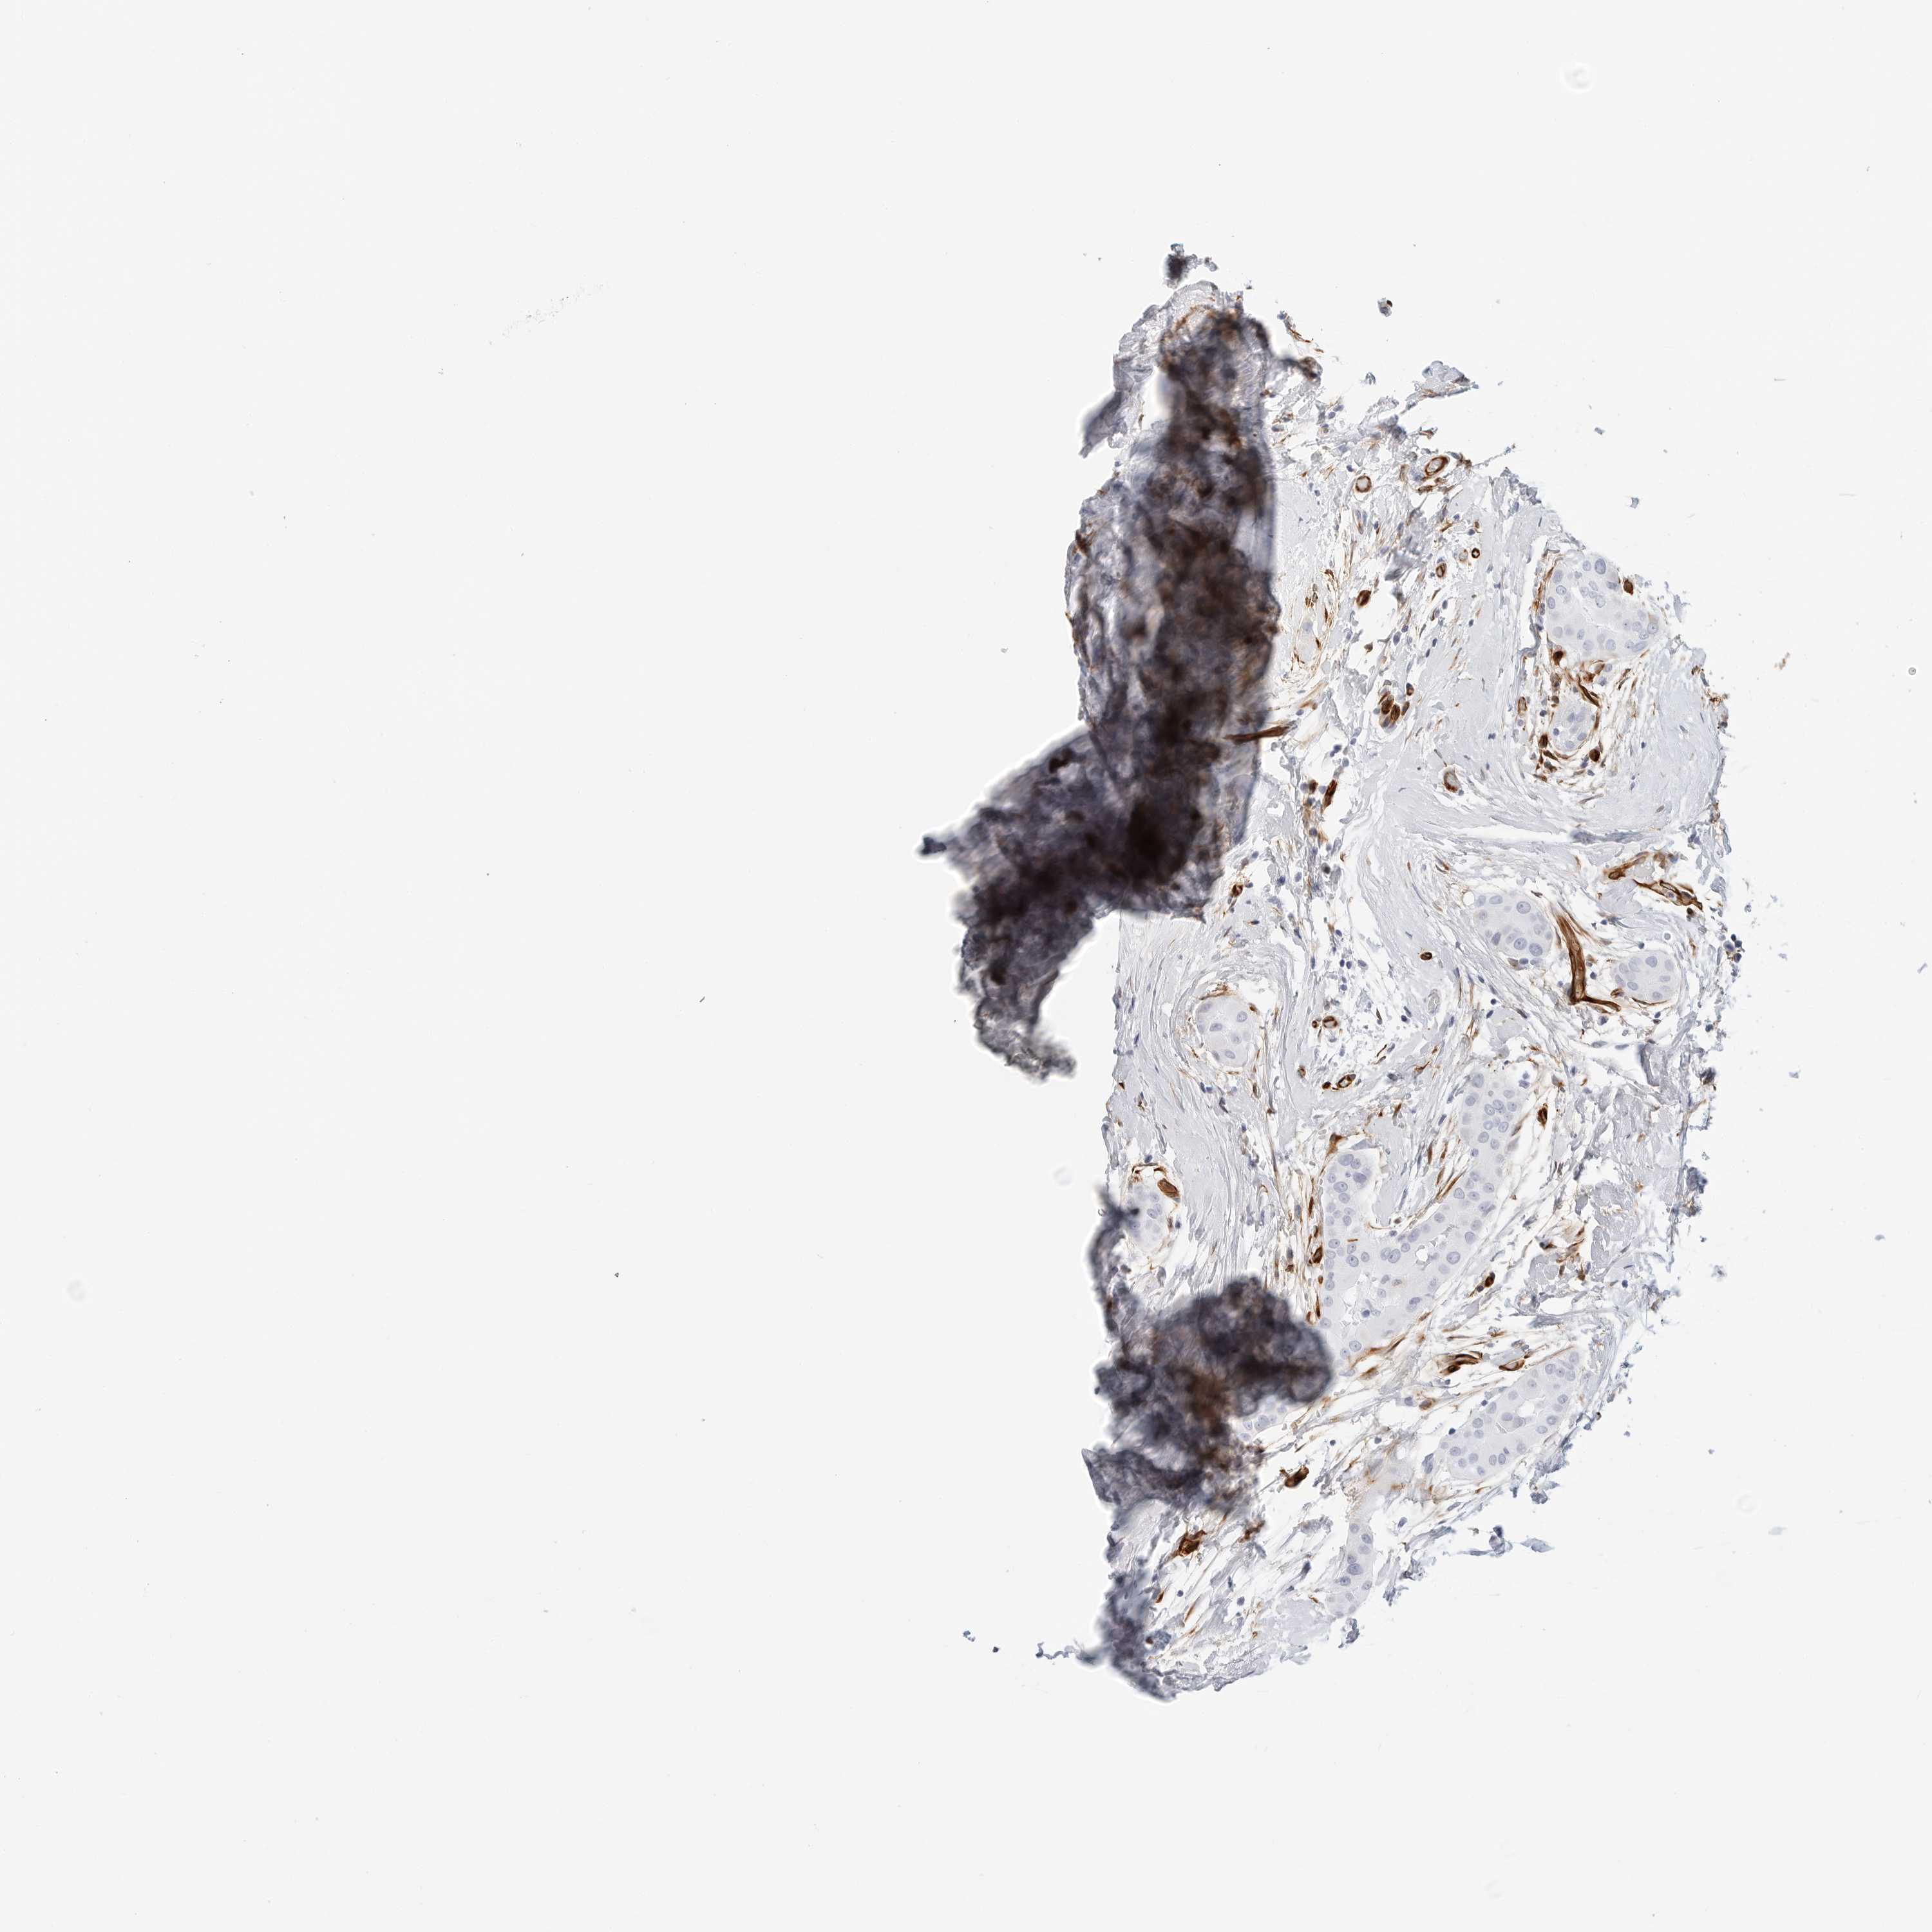

THYROID CANCER - Protein expressioni

A mouse-over function shows sample information and annotation data. Click on an image to view it in a full screen mode. Samples can be filtered based on level of antibody staining by selecting one or several of the following categories: high, medium, low and not detected. The assay and annotation is described here.

Note that samples used for immunohistochemistry by the Human Protein Atlas do not correspond to samples in the TCGA dataset.

Antibody stainingi

Antibody staining in the annotated cell types in the current human tissue is reported as not detected, low, medium, or high, based on conventional immunohistochemistry profiling in selected tissues. This score is based on the combination of the staining intensity and fraction of stained cells.

Each image is clickable and will lead to virtual microscopy that enables deeper exploration of all samples and also displays staining intensity scores, fraction scores and subcellular localization as well as patient and tissue information for each sample.

Antibody HPA007007

Antibody HPA026111

Antibody CAB005889

Antibody CAB058692

Staining

High

Medium

Low

Not detected

Intensity

Strong

Moderate

Weak

Negative

Quantity

>75%

75%-25%

<25%

None

Location

Nuclear

Cytoplasmic/membranous

Cytoplasmic/membranous,nuclear

Papillary adenocarcinoma, NOS

Follicular adenoma carcinoma, NOS